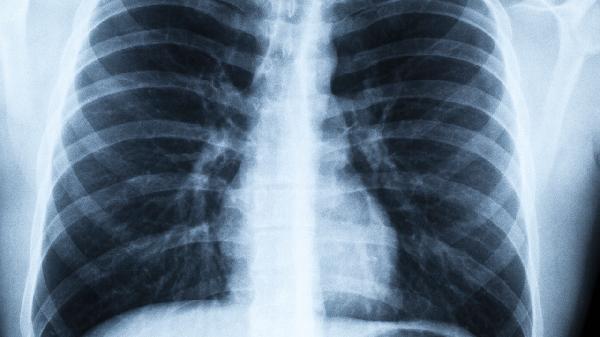

这些症状虽然特异.性不高,但确实是身体发出的预警信号。特别是长期吸烟、有肿瘤家族史的高危人群,更要提高警惕。建议发现异常及时就医检查,胸部低剂量CT是目前筛查早期肺癌的有效手段。记住,早发现早干预才是应对疾病的关键!